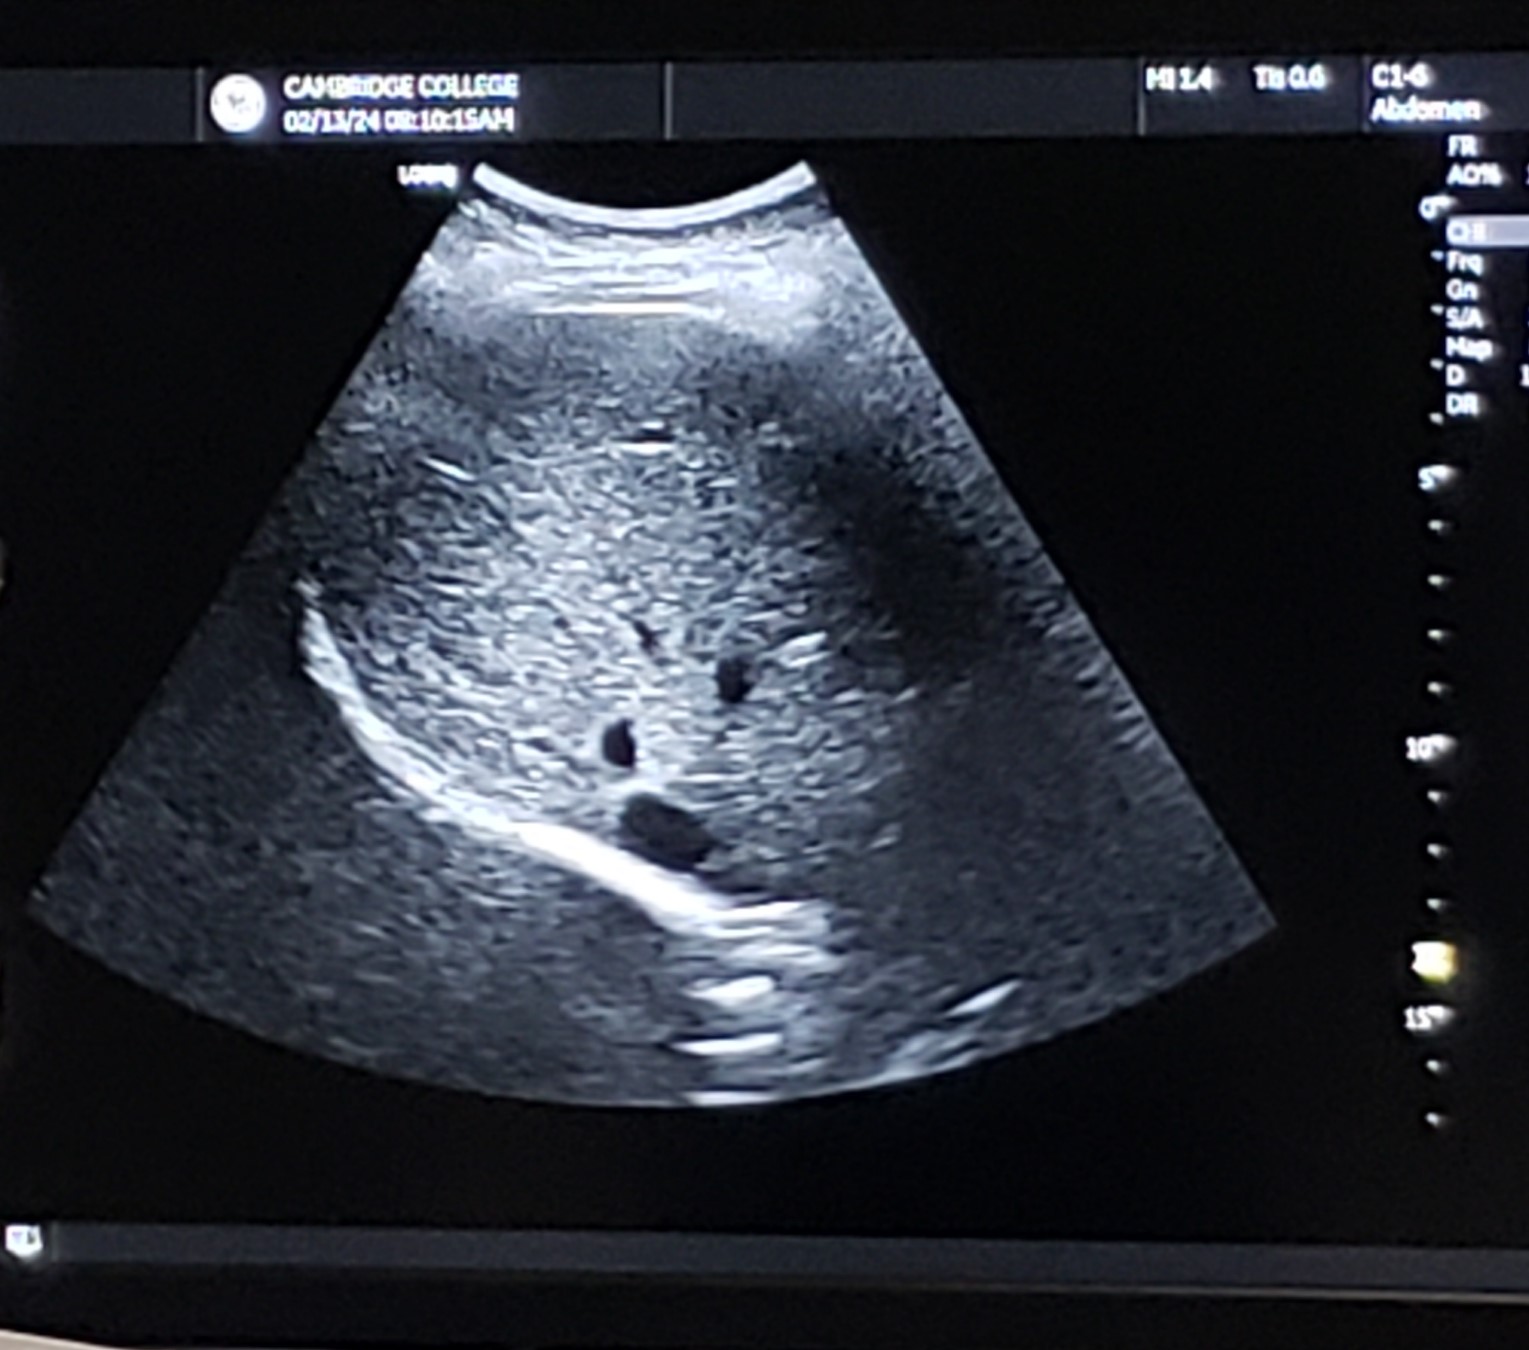

Trans RLL w/ MPV - grayscale

14